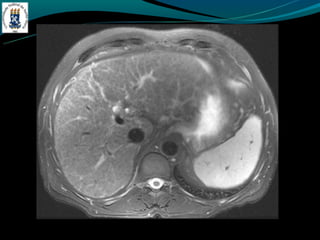

-   RM: identificar esteatose focal

DOENÇA DO FÍGADOGORDUROSO -E uma resposta uma lesão e a toxina -Acúmulo de colesterol e triglicerídios -Alcoolismo, obesidade, desnutrição, hiperalimentação, costicóide, DM, pancreatite … -Exames de imagem é o melhor método -Avaliação: - TC: densidade menor do que do baço - RM: identificar esteatose focal -Esteatose focal - Distribuição segmentar, sub capsular, VB, lig falciforme - Margem nítida e em linha reta - Não desloca vasos